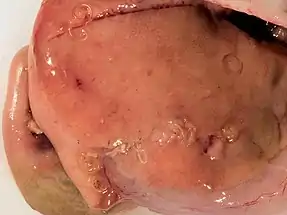

A typical endoscopy of the acute gastric form shows a worm embedded within the submucosa, with a visible lesion at the site of entry, and a thicker oedematous stomach lining.[3] In patients with chronic gastric infection, there is often an ulcer or inflamed mass visible on the stomach lining.[3]

Intestinal anisakiasis can be detected approximately one week after ingestion.[8] Similar to the gastric form, the terminal ileum bears a lesion through which the larva has penetrated into the submucosa.[3] The intestinal lining becomes inflamed and can triple in its thickness, swollen masses are present, and the lumen becomes constricted.[3]